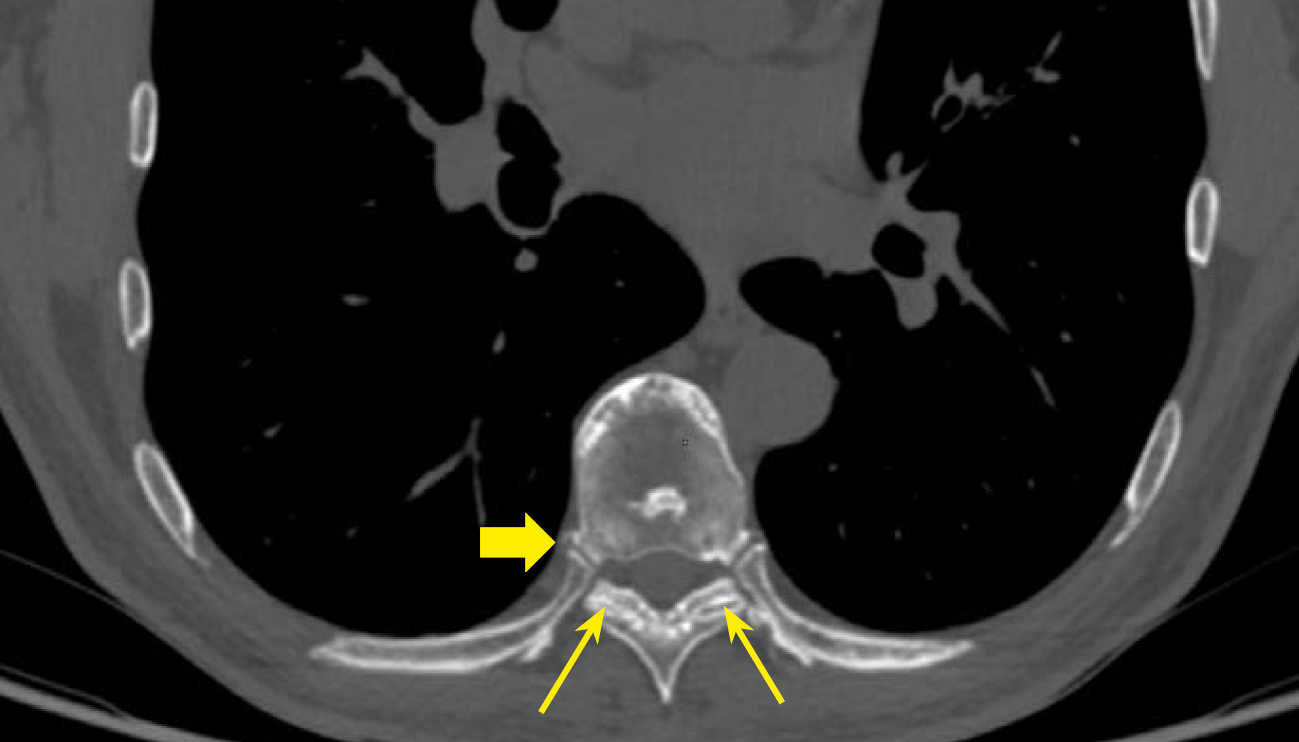

Рисунок 2. МСКТ пациента А. с акромегалией 37 лет, аксиальная проекция (склероз субхондральных отделов с сужением суставной щели, тонкие стрелки), ОА реберно-позвоночных суставов (склероз субхондральных отделов с наличием остеофитов, толстая стрелка).

Figure 2. MSCT of patient A. with acromegaly, 37 years old, axial view (sclerosis of subchondral regions with joint space narrowing, thin arrows), OA of costovertebral joints (sclerosis of subchondral regions with osteophytes, thick arrow).

В нашем исследовании проведен анализ патологии позвоночника и суставов у пациентов с акромегалией. Спондилоартроз выявлен почти у всех пациентов — 95,9%, чуть реже визуализирован ОА реберно-позвоночных суставов 89,8% и ОА грудино-реберных суставов в 75,9% случаев (табл. 3, рис. 2–5).